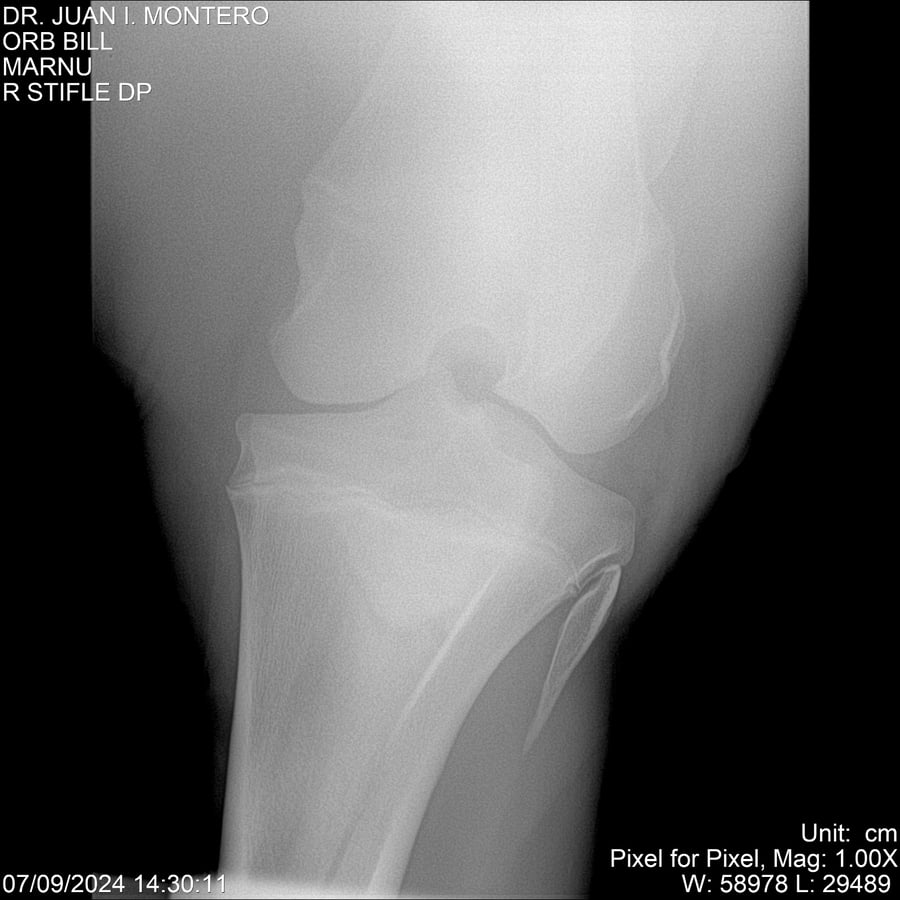

LOTE 7, ORB BILL 🔥 🔥 🔥 Lote Anterior Volver al remate Lote Siguiente Ficha Contacto Montevideo - Ficha del Lote Identificador: #282523 Categoría: Yeguarizos Montevideo - 83 Visualizaciones ClicData Contacto Empresa: Abelenda N. R., Walter Hugo Nombre*: Teléfono* : E-mail* : Mensaje Enviar Registrese gratis Este contenido Exclusivo está disponible sólo para usuarios registrados Ingresar